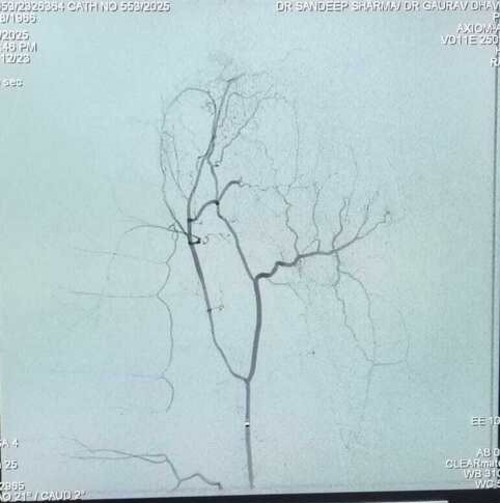

Balwinder Kaur Journey to Knee Pain Relief: A Successful GAE Treatment Story

Genicular Artery Embolization